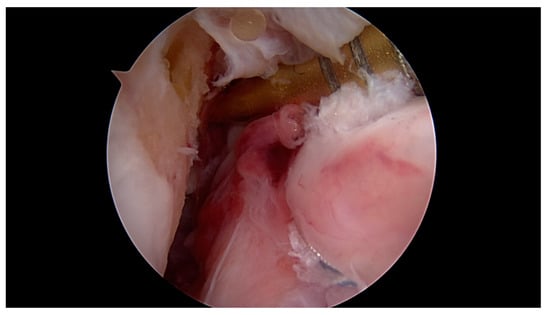

All surgeries were performed under spinal anaesthesia with the affected leg placed in an adjustable leg holder and with administration of an intravenous antibiotic prophylaxis. An examination under anaesthesia of the knee was performed prior to surgery in order to confirm ACL instability. The standard anterolateral and anteromedial portals were established to perform the arthroscopy to confirm all suspected findings with a probe. The ACL was assessed regarding tear pattern and tissue quality. When a proximal tear pattern with good tissue quality was identified (Figure 2), the patient was deemed eligible for arthroscopic ACL repair using SA: a labral scorpion suture passer (Arthrex, Naples, FL, USA) was used to pass a No. 2 FiberWire® (Arthrex, Naples, FL, USA) 3 times approximately 1 cm distal to the tear through the ACL remnant (Figure 3 and Figure 4). The femoral tunnel was drilled in anatomic manner within the footprint with 130 degrees knee flexion using a spade tip drill pin (Arthrex, Naples, FL, USA). An arthroscopic 45 degrees awl was used to perform a microfracture near the femoral footprint to enhance healing (Figure 5). Afterwards, a shuttling loop was passed through the femoral tunnel. The tibial drilling guide (Smith and Nephew, Andover, MA, USA) was placed at the anterior centre of the tibial footprint and a small skin incision at the anteromedial aspect of the proximal tibia was established to allow drilling and shuttling of a loop through the tibial tunnel. The tibial and femoral shuttling loop as well as the FiberWire® suture were retrieved through the anteromedial portal, the latter two placed in the tibial shuttling loop and passed through the tibial tunnel. Using the femoral shuttling loop, the SA construct containing a FiberTape® (Arthrex, Naples, FL, USA) armed TightRope® (Arthrex, Naples, FL, USA) and the FiberWire® were carefully shuttled through tibia and femur so that the TightRope® button flipped at the femoral cortex. The FiberTape® was fixed distally at the anteromedial tibia with a 4.75 SwiveLock® (Arthrex, Naples, FL, USA) with the knee in full extension. Subsequently, the FiberWire® suture and TightRope® tensioning suture were knotted on tension completing the ACL repair (Figure 6). Concomitant meniscal injuries were addressed either with direct repair (RapidLoc®, Mitek Products, Westwood, MA, USA) or with cautious partial resection when repair was deemed not feasible due to the configuration of the tear or pre-existing degenerative meniscopathy (Table 1). Concomitant chondral injuries were carefully smoothed or prudently underwent nano-fracture under direct vision.

Figure 2. Proximal ACL tear 5 h after injury with excellent tissue quality and intact synovial coverage of the ACL remnant.